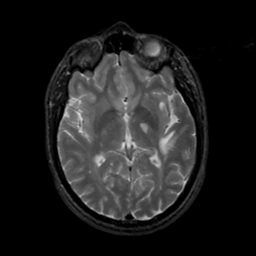

MR Study #6, March 17, 1991 -- Slice #25